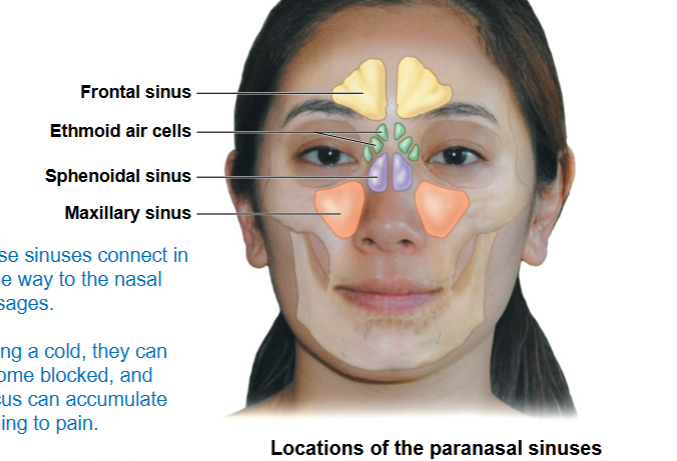

pneumatized bone

The Paranasal Sinuses

-Air-filled chambers that open into the nasal cavity:

• Frontal sinuses

• Sphenoidal sinuses

• Maxillary sinuses

• Ethmoid air cells

What category of bone do these fall into knowing they have hollow spaces in

them?

frontal sinus, ethmoid air cells, sphenoidal sinus, maxillary sinus

these connect in some way to the nasal passages. During a cold, they can become blocked, and mucus can accumulate leading to pain

do not

paranasal sinuses (do or do not) lie in the same coronal plane?